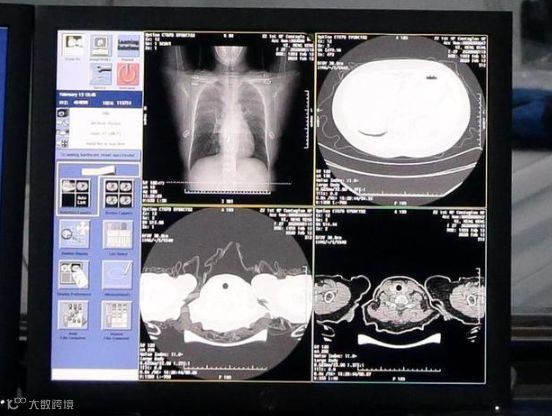

人工智能机器人

疾病预防

诊断及筛查